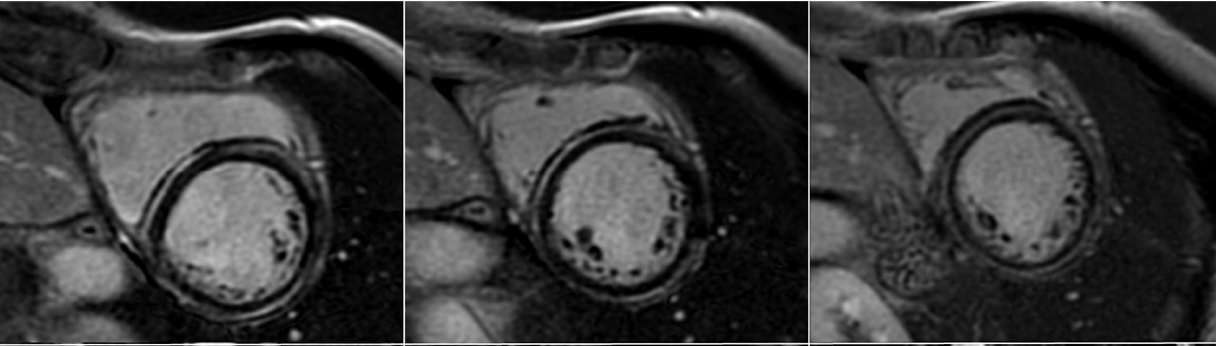

La velocità di progressione della fibrosi cardiaca: un nuovo orizzonte

La velocità di progressione della fibrosi cardiaca emerge come un nuovo e cruciale indicatore prognostico nella cardiomiopatia ipertrofica. Un recente studio evidenzia come l’LGE rate sia più predittivo degli eventi avversi rispetto alla semplice estensione della fibrosi, aprendo nuove prospettive per il monitoraggio e la gestione terapeutica dei pazienti.